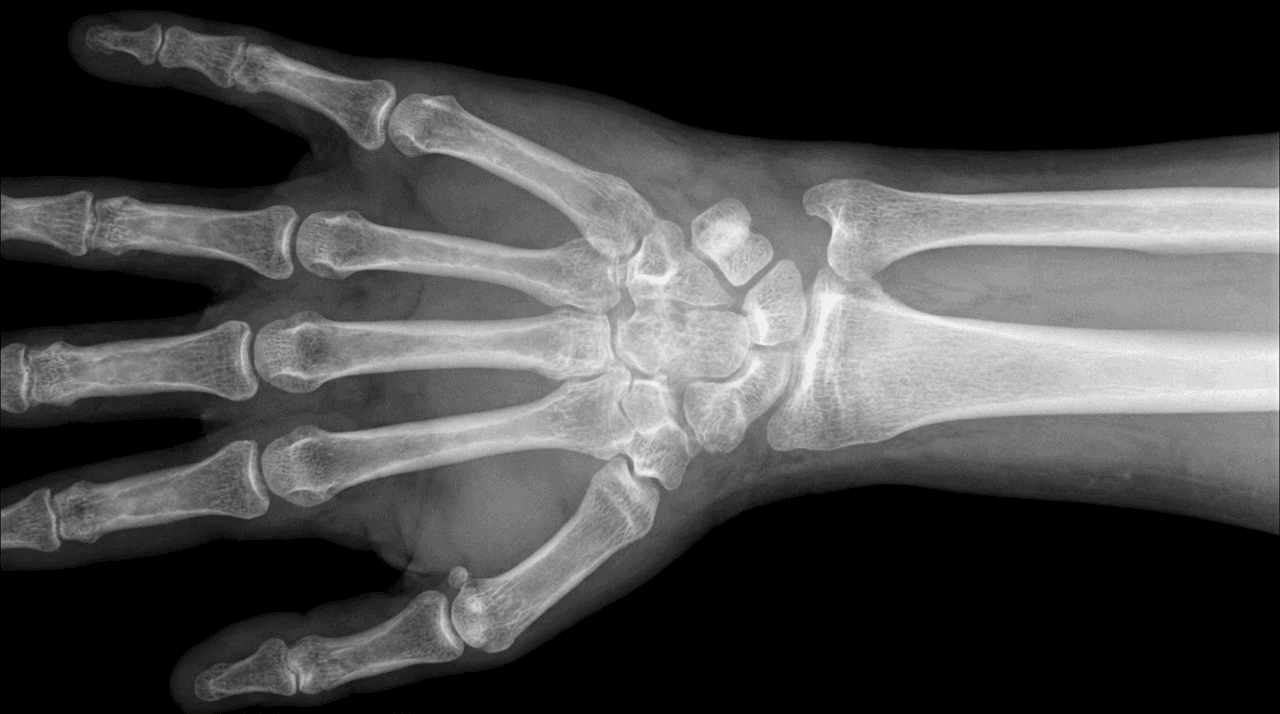

Dr. Farid Ghasemzadeh Mojaveri is a distinguished orthopedic hand specialist in Dubai focusing on specialized upper limb and trauma care. Recognized as one of the best hand surgeons in Dubai, Dr. Farid understands that the hand and wrist contain intricate networks of bones, nerves, and tendons. Successful treatment requires the highly specialized expertise of a dedicated hand specialist doctor.

Dr. Farid specializes in the surgical and non-surgical management of the full range of disorders. Our expertise ensures you receive the most targeted care from a leading hand specialist doctor.